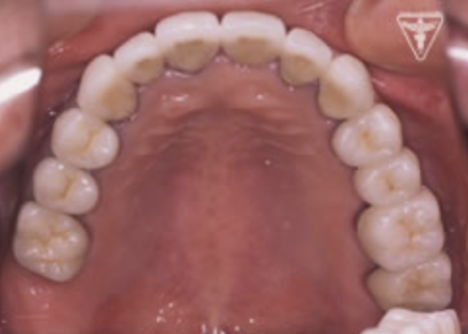

初診時の正面観・側方観・かみ合わせの面の状態を示します。

下の顎のずれがあるのを確認して下さい。

治療後

初期治療を経て歯周外科、歯内療法により病巣の消失が認められ改善された。

咬んだ感じが軽くなり、よく咬めると評価を頂きました。